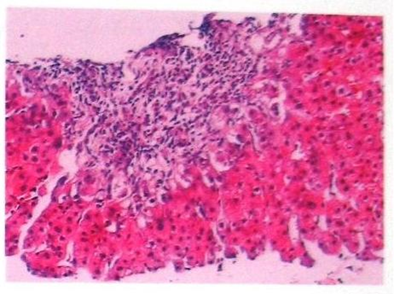

现病史:患者于20年前(2001年3月份)因肝功能异常查出肝硬化腹水,在我院住院治疗半月好转出院。2004年因肝硬化脾脏肿大、脾功能亢进,在我院行脾脏切除加门奇静脉断流手术后,病情有所好转。病毒性肝炎甲、乙、丙、丁、戊型标志物均阴性,建议其做肝穿刺活检,以明确病因,患者拒绝。2008年2月11日查胃镜:①食道静脉中度曲张、红色征(+),②门脉高压性胃病,在我院内镜下行食管静脉套扎治疗。自身免疫性肝病抗体结果:ANA弱阳性 斑点型,SMA、AMA、AMA-M2、LKM、LKM-1、LC-1、抗Ro-52、抗3E(BPO)、抗Sp100、抗PML、抗gp210、ASMA、抗肝抗原、SLA/LP:均为阴性。在彩超引导下行肝脏穿刺活检术,病理标本送中日友好医院病理科。病理结果回报:肝穿组织内汇管区扩大,部分纤维化相连成纤维隔,分隔肝实质。汇管区内轻-中度慢性炎细胞浸润,多数汇管区炎灶内或小动脉旁纤维化区缺小胆管,易见散在或灶状聚集的D-PAS+的吞噬细胞。汇管区周围肝细胞明显胆盐淤积,可见Mallory小体(提示有慢性胆汁淤积)。肝小叶内散在少数小坏死灶,Kupffer细胞增生活跃,并可见D-PAS(+)吞噬细胞呈灶状聚集。病理诊断:(肝穿)肝内胆管缺乏综合征,肝纤维化,III期。与病理科会诊,诊断为:自身免疫性胆管炎。肝穿图如下:

HE染色,放大200倍